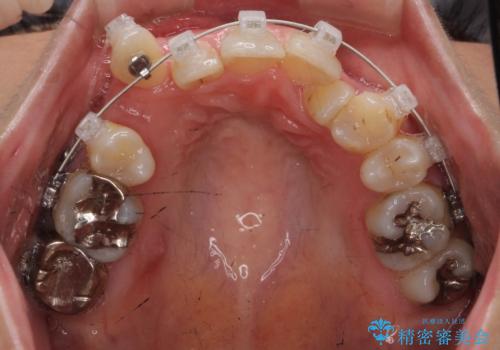

- 矯正装置

- ワイヤー矯正

- 前歯のがたつきを主訴に来院されました。

小さいころ下の小臼歯を2本抜いたとのことでした。

上の歯を2本抜歯して矯正しています。

また、右上の7番(一番後ろの歯)の状態が悪く、根尖病変がありました。根の治療をする選択肢もありましたが、歯質も薄く、予算的にも治療が難しかったため、抜歯して親知らずを並べています。